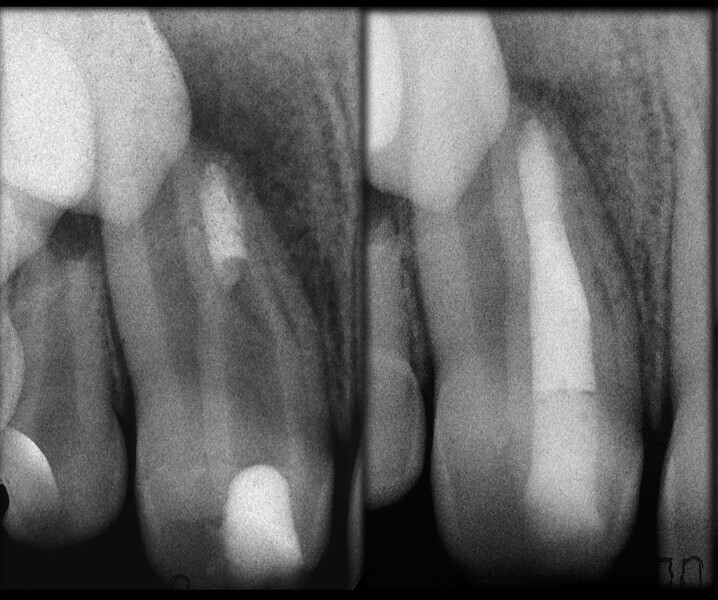

Use of 3D technology in the diagnosis and treatment of endodontic disease